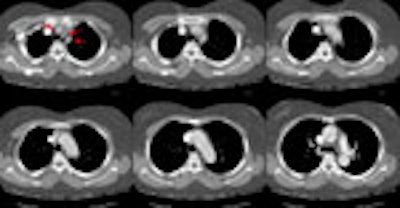

A chest CT was dome due to the severity of the patients symptoms. The

scan demonstrated an aortic dissection involving both the ascending and

descending aorta. The images of the chest revealed that the dissection

extended into the great vessels arising from the aortic arch (red arrows).